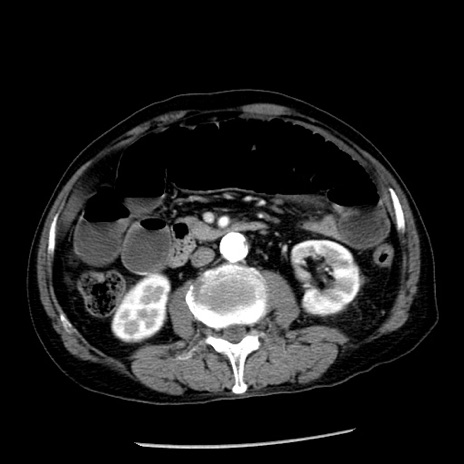

症例26(横断像)

【症例】80歳代男性

【主訴】嘔吐

【現病歴】昨晩2回嘔吐あり、今朝になっても嘔吐あり。来院。

【既往歴】胃潰瘍

【身体所見】意識清明、BT 37.6℃、BP 166/95mmHg、HR 100bpm、SpO2 97%、腹部:平坦・軟、腸蠕動音聴取良好、圧痛なし。

【データ】WBC 21900、CRP 1.46